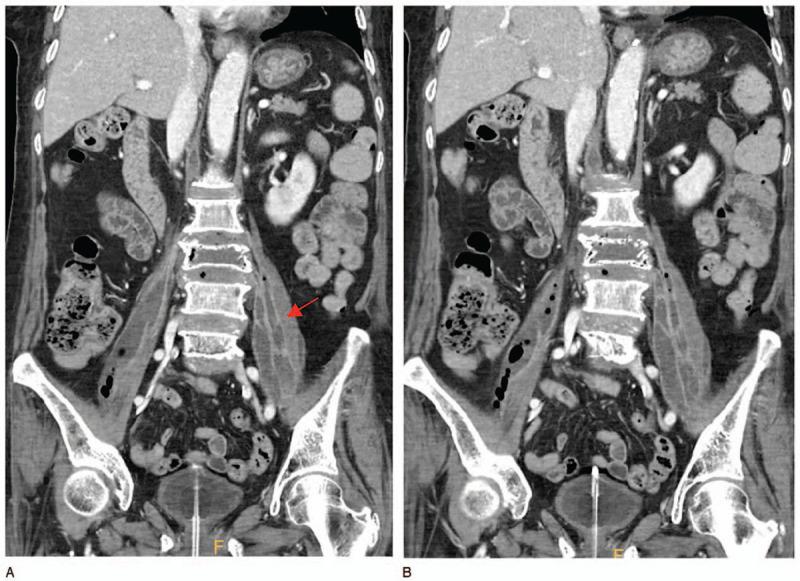

腰大肌脓肿是一种罕见但可能具有毁灭性的疾病,与神经功能缺损、感染性休克甚至死亡风险相关。目前的一线治疗方法是在影像引导下进行经皮导管引流(PCD),并联合使用广谱抗生素。如果PCD失败或无法进行,则应考虑手术引流。尽管已经出现了许多关于PCD和开放手术引流的研究,但腹腔镜引流的结果很少被报道。因此,我们对6例患者的腰大肌脓肿进行了腹腔镜引流;引流彻底,未出现复发或并发症。所有患者均通过X线平片、增强CT和实验室检查进行评估;所有患者均随访1年。当PCD失败时,腹腔镜引流是一种很好的治疗选择,具有开放手术的所有优点(彻底引流、切除感染组织以及同时治疗伴发病变)。此外,腹腔镜引流微创,切口小,恢复快。